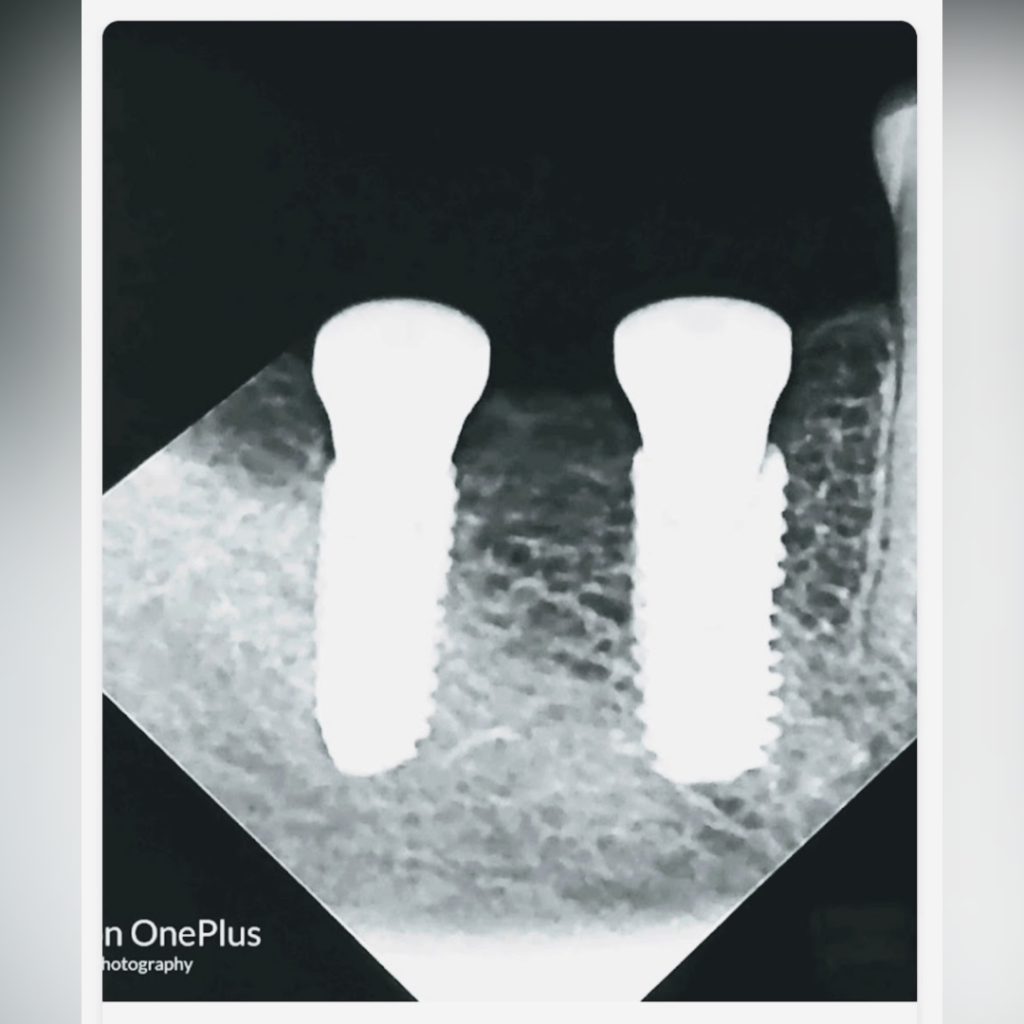

Dental implants are artificial tooth roots made of titanium that are surgically placed into the jawbone to support replacement teeth such as crowns, bridges, or dentures.

Titanium is a biocompatible material that integrates naturally with the bone through a process called osseointegration. Once the implant fuses with the jawbone, it creates a stable foundation for a replacement tooth that looks and functions like a natural tooth.

A dental implant typically consists of three components:

1. Implant Fixture

A titanium screw placed into the jawbone that acts as the artificial tooth root.

Step 3: Implant Placement

During this stage, the titanium implant is placed into the jawbone under local anesthesia. The procedure is generally comfortable and minimally invasive.

Step 4: Healing and Osseointegration

The implant requires a healing period of 3–4 months, during which the implant integrates with the jawbone.

This process is crucial for creating a strong and stable foundation for the replacement tooth.